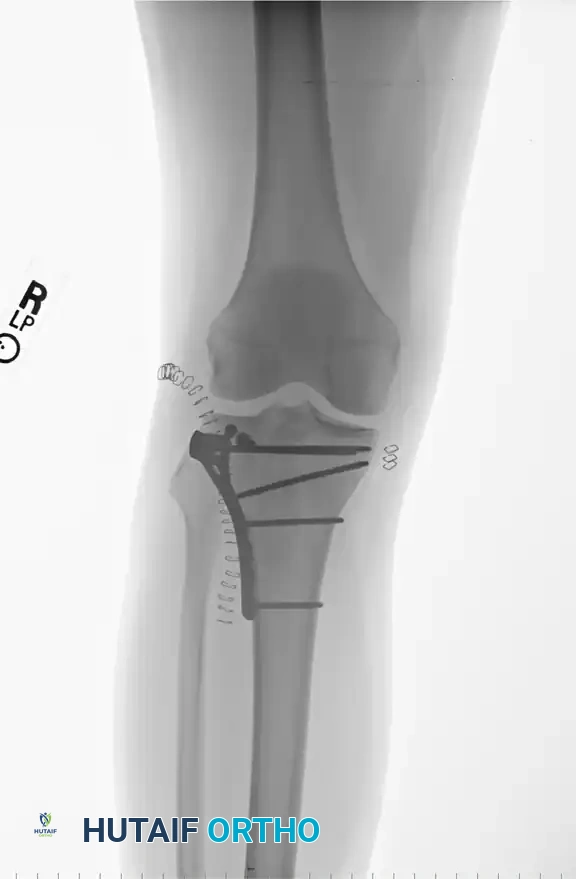

5. Fixation: The lateral cortex is supported with a pre-contoured lateral periarticular locking plate acting as a buttress.

3. Fixation: This approach allows direct access to the posteromedial apex of the fracture. An anti-glide or buttress plate is applied to resist the sheer forces of the medial femoral condyle.

* Hybrid Fixation: The modern gold standard for these severe injuries is a hybrid approach. A method of lateral plateau plating combined with temporary medial external fixation (as described by Mast) is highly effective. Alternatively, limited open reduction of the articular surface with percutaneous screw fixation, followed by the application of an Ilizarov fine-wire circular frame, provides excellent biomechanical stability while completely respecting the biology of the traumatized soft tissues.